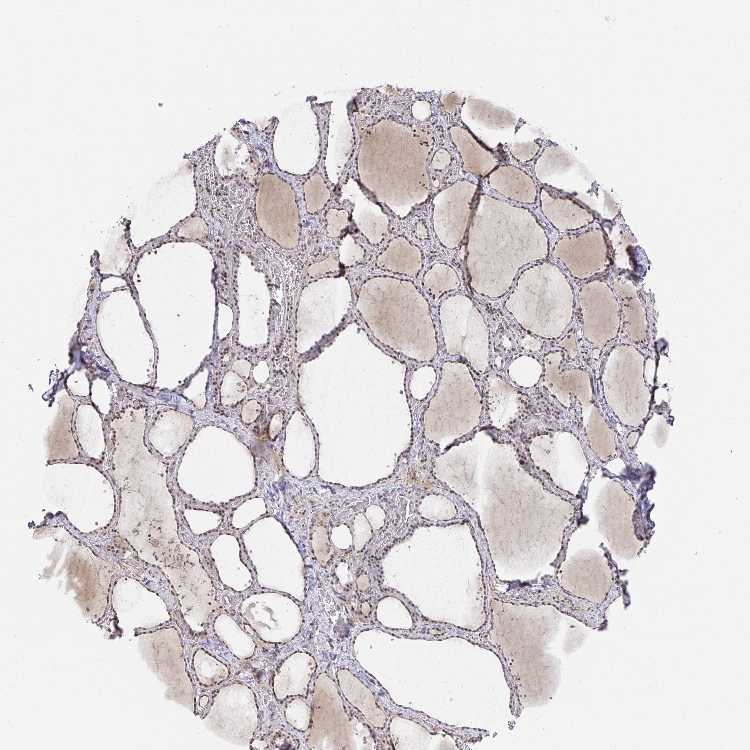

TISSUE PRIMARY DATA THYROID GLAND Show tissue menu

Thyroid gland

THYROID GLAND - Antibody stainingi

Antibody staining in the annotated cell types in the current human tissue is reported as not detected, low, medium, or high, based on conventional immunohistochemistry profiling in selected tissues. This score is based on the combination of the staining intensity and fraction of stained cells.

Each image is clickable and will lead to virtual microscopy that enables deeper exploration of all samples and also displays staining intensity scores, fraction scores and subcellular localization as well as patient and tissue information for each sample.

Antibody HPA050714Antibody CAB039243Antibody CAB039244

Glandular cells MediumHighHigh